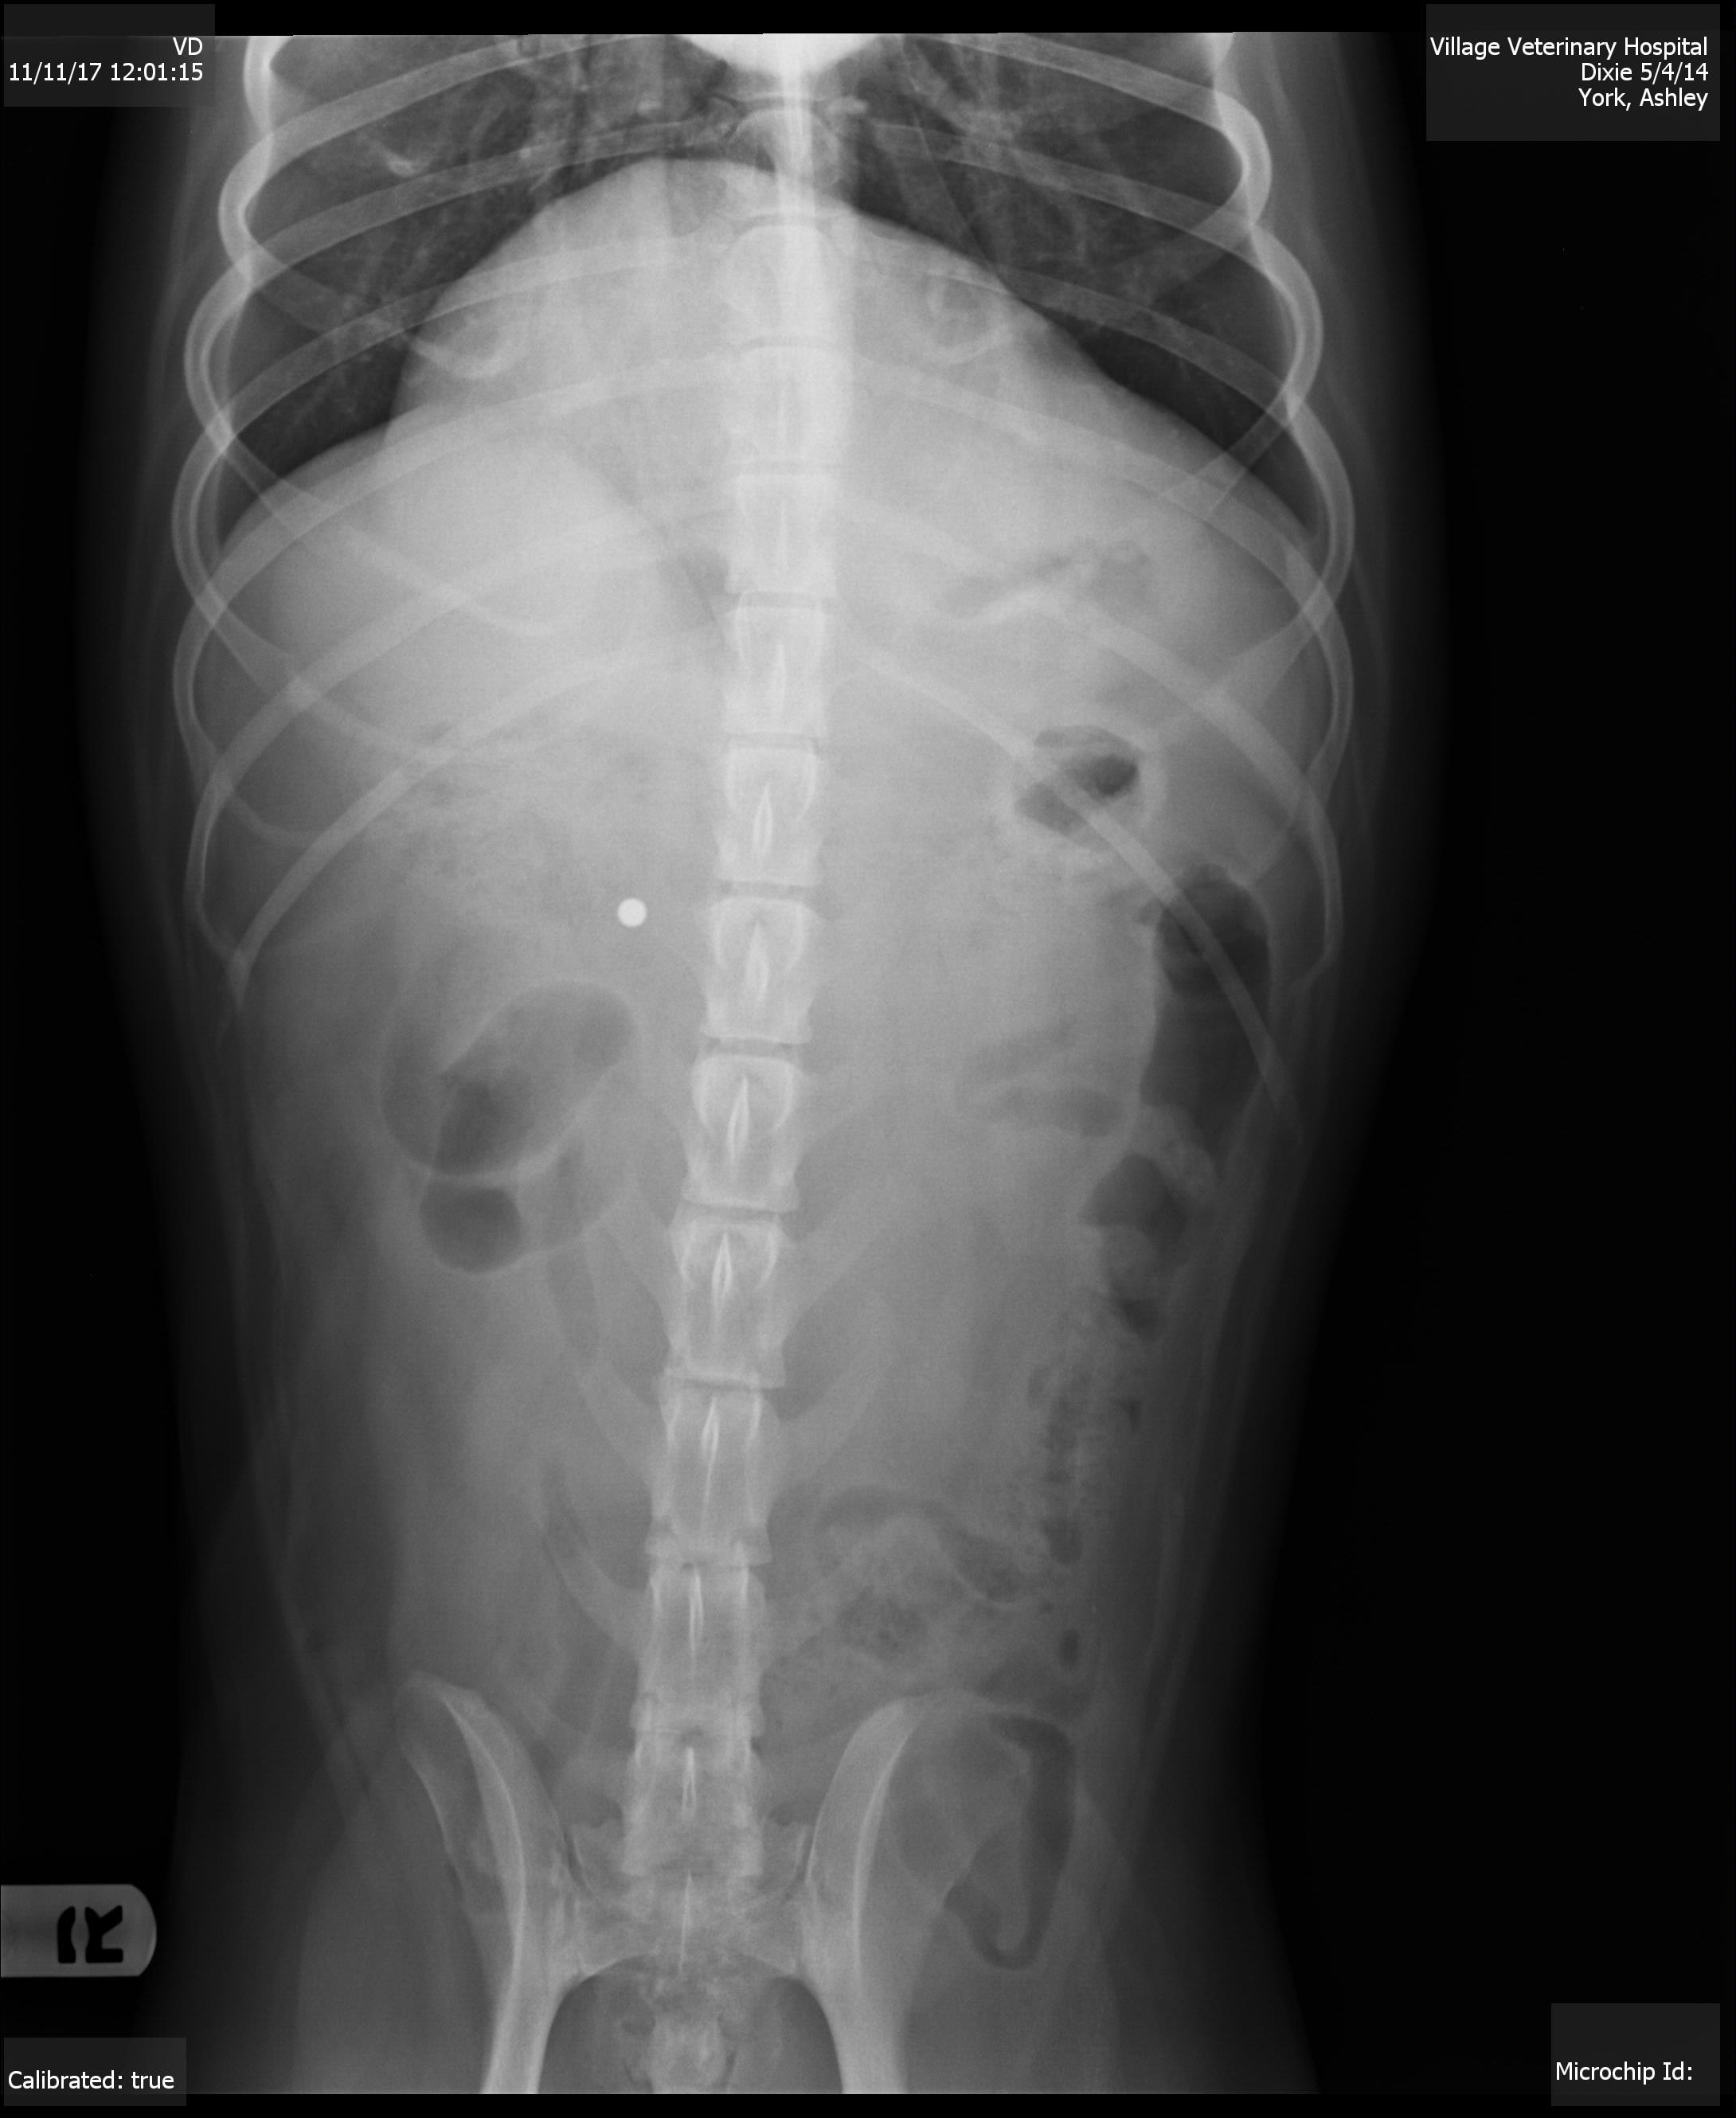

My dog keeps gagging/choking & licking/swallowing a lot,this started last Wed,she threw up bile Wed.morning,ate dinner that night,threw up bile Thurs.morning & night & did not eat all day Thurs,ate Fri,hasn't vomited since but still not much of an appetite & keeps gagging,we ran a chem17 w/lytes & that came back normal besides she was 0.1 low from norm. on her potassium levels,we took an xray of her abdomen & that looks fine as well, other than waiting until Mon to do chest xrays idk what todo

I am sorry that Dixie is so sick. In this type of situation I am still usually very suspicious of an intestinal foreign object. There is one area on the x-Ray that is a little suspicious to me. Make sure to look under her tongue for any thread or string caught. I would typically recommend either a barium series or an abdominal ultrasound at this time. Occasionally exploratory surgery is recommended if we can’t find another answer . Best of luck and I hope she improves soon.